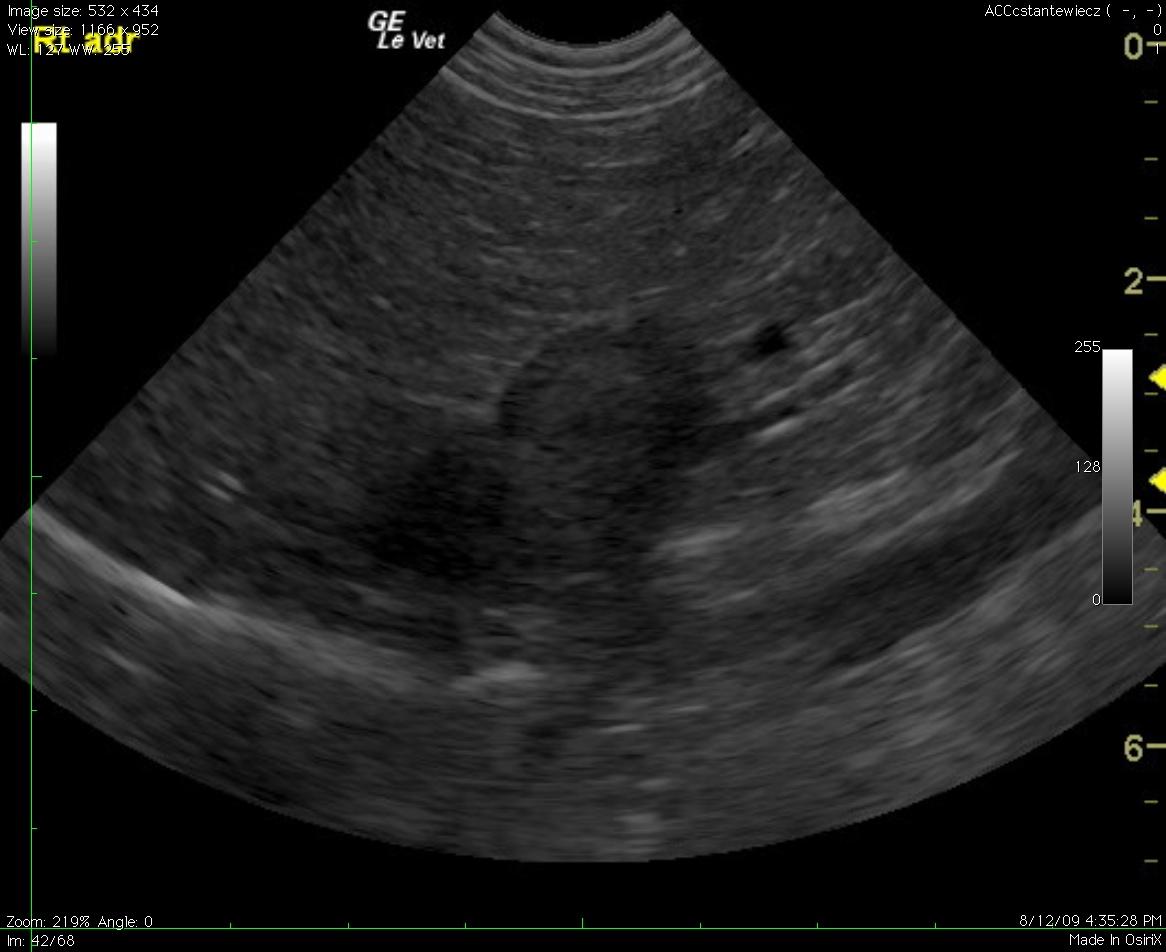

A 13-year-old MN Jack Russell Terrier dog presented for a second opinion with panting, weakness, and anorexia. The physical exam revealed mild gingival pallor and mild tachypnea. Complete blood count revealed strongly regenerative anemia (HCT 22%) with spherocytes, marked polychromasia, anisocytosis, and moderate neutrophilic leukocytosis. Blood chemistry revealed only slight azotemia. In house 4Dx was negative. Blood pressure was 159/98. Urinalysis was pending at the time of the sonogram but urination was reported to be normal.

A 13-year-old MN Jack Russell Terrier dog presented for a second opinion with panting, weakness, and anorexia. The physical exam revealed mild gingival pallor and mild tachypnea. Complete blood count revealed strongly regenerative anemia (HCT 22%) with spherocytes, marked polychromasia, anisocytosis, and moderate neutrophilic leukocytosis. Blood chemistry revealed only slight azotemia. In house 4Dx was negative. Blood pressure was 159/98. Urinalysis was pending at the time of the sonogram but urination was reported to be normal.